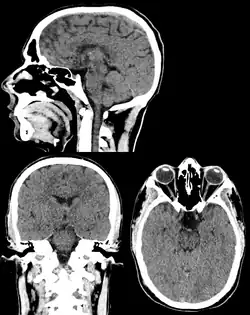

Head & Neck Imaging

CT scan remains the cornerstone imaging modality for the initial evaluation and subsequent management of patients with acute traumatic brain injury due to its rapid acquisition time and high sensitivity for detecting hemorrhagic complications, such as intraparenchymal hematomas and subdural hemorrhages.[56] CT scan of the head is typically used to detect infarction (stroke), tumors, calcifications, haemorrhage.[57] Tumors can be detected by the swelling and anatomical distortion they cause, or by surrounding edema. CT scanning of the head is also used in CT-guided stereotactic surgery and radiosurgery for treatment of intracranial tumors, arteriovenous malformations, and other surgically treatable conditions using a device known as the N-localizer.[58][59][60][61][62][63]

Non-contrast CT

CT procedure in which contrast media is not used is often called as Non-Contrast CT (NCCT) or plain CT. This procedure is employed when there is already a sufficient contrast distinction in the target tissues, rendering the resulting image diagnostically significant. The process involves acquiring a topogram, followed by scanning the region of interest and reconstructing the data, marking the conclusion of the procedure. The non-contrast CT scans are rapid, less hazardous, and cost-effective procedures. Non-contrast CT head scans are useful in the identification of various conditions, encompassing traumatic hemorrhages, subdural hematomas, cerebral edema, fractures, and in detecting foreign bodies, such as tempered glass, in emergency situation.[134]